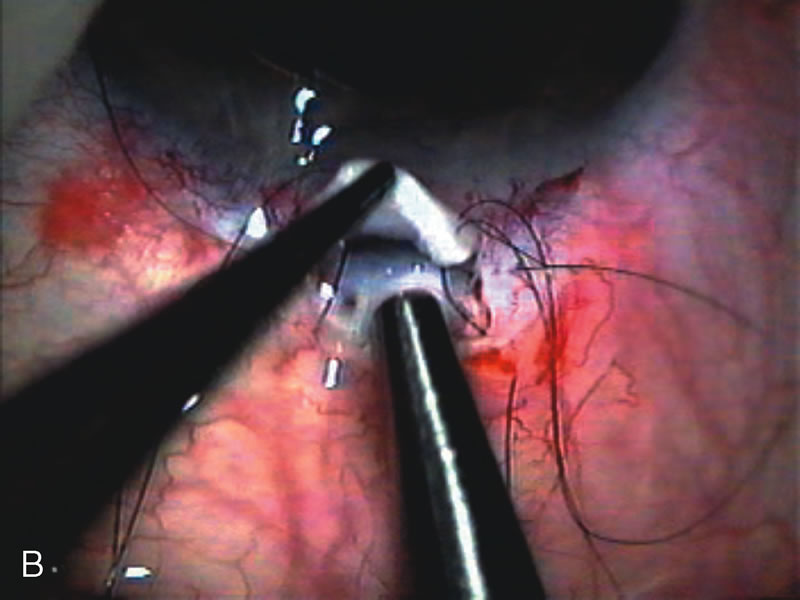

Fig. 7. Phacotrabeculectomy adjacent to a failed filter in cataractous eye. The ability to combine small-incision cataract extraction with trabeculectomy all through the same incision adjacent to the failed filter allows the surgeon to work in a familiar superior area. Avoiding incisions into the existing bleb decreases conjunctival buttonholes, hypotony, operating room time, and subconjunctival bleeding. A. Appearance of failed bleb with exposure of superior temporal quadrant gained with a corneal traction suture. B. Prepare a limbus-based conjunctival flap and a scleral flap. C. This bleb is at high risk to fail again justifying the need for MMC, 0.2 mg/cc applied on a pledget for 4 minutes. D. Insert the keratome and perform phacotrabeculectomy in the usual fashion.

The inflammation associated with lens extraction at any site usually causes complete failure of a marginal functioning bleb. In addition, pressure reduction by medical means is usually minimal in these recalcitrant cases, and combined surgery is indicated. In the past, these cases were approached with large-incision ECCE, clear corneal cataract incision, and bleb revision. Drawbacks included those mentioned earlier for large incision clear corneal cataract extraction, and bleb revision is often associated with conjunctival buttonholes, wound leaks, subconjunctival hematoma, destruction of friable sclera, and associated hypotony. With the advent of modern-day cataract surgery, a phacotrabeculectomy is often possible adjacent to the failed filter (Fig. 7). The ability to combine cataract extraction with implant and filtration surgery all through the same small incision has greatly improved outcomes for patients with marginal preoperative filters. There are several other viable options in this case. If the surgeon elects to remove the cataract through a temporal clear corneal incision, the bleb may be revised or a new adjacent filter fashioned. As mentioned earlier, revising a failed filter is technically challenging. If the surgeon believes it is not feasible to revise the filter or fashion a new one, a glaucoma drainage implant is a reasonable option combined with temporal lens extraction.172